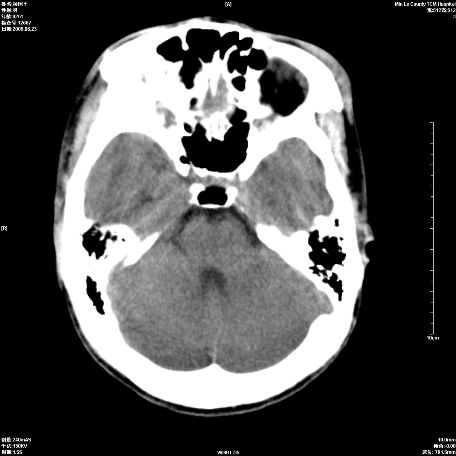

以下是引用zxl51642在2009-6-23 14:15:00的发言:[br]1、颅内未见血肿,颅骨未见骨折;[br]2、双侧苍白球对称性钙化,透明隔间腔及verga氏腔形成。